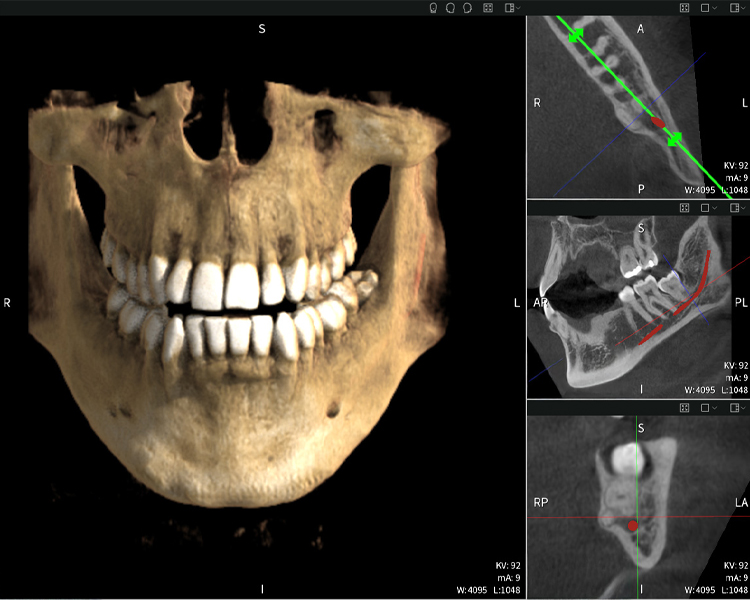

Abbildungen b–d zeigen verschiedene Ansichten einer 3D-Rekonstruktion des Unterkiefers und bieten eine umfassende Übersicht über die Anatomie des Unterkiefers, die Lage der Nerven im Verhältnis zu den Zähnen und ermöglichen die Beurteilung der Zahnsymmetrie und Ausrichtung.

Abbildung d zeigt den bereits vorbehandelte Zahn 48, dessen Krone entfernt wurde und dessen Wurzeln nahe am Nerv belassen wurden, was das hohe Risiko einer Nervenschädigung verdeutlicht.